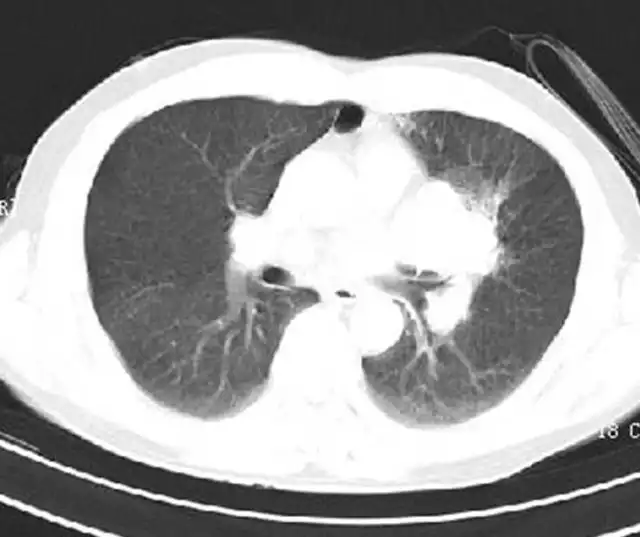

胸部:气管分叉管壁增厚,右肺上叶前段软组织结节形成,考虑肿瘤性病变可能大。

病例分析二(周围型肺Ca):

影像检查: